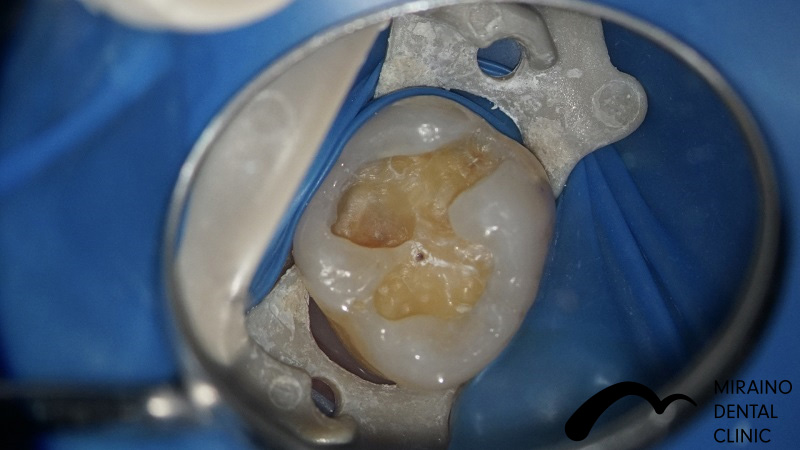

Case1

| 施術名 | 無菌的根管治療 |

| 治療の概要 | 噛んだ時の違和感・歯ぐきにできものができるということで来院されました。 過去に神経の治療を行なっている場所の再発でした。 治療中の唾液による感染を防止するため、 ラバーダムを用いて無菌的に歯の根の中・根の先の感染の除去治療を行いました。 6ヶ月経過観察後、感染再発の症状が見られなかったため、 汚れのつきにくい素材で被せ物を装着しました。 |

クリックして詳細を表示

| 施術の内容 | 歯の根の中・根の先の感染の除去します。 ラバーダムを用いて唾液による感染のリスクを排除し無菌的な治療を行います。 感染・炎症の所見が無くなれば抗菌作用のある材料で根っこの通り道を封鎖します。 ラバーダム を用いて唾液による感染のリスクを排除し無菌的な治療を行います。 |

| 1歯あたりの治療費 | 1根:15,000円 |

| 考えられるリスク、副作用[歯科治療] | 治療後、痛みや違和感、出血、腫れ、麻痺などが出る事があります。 |

| 考えられるリスク、副作用[全てにおいて] | 必ずしもご希望通りにならない事があります。 |

| 考えられるリスク、副作用[麻酔] | 麻酔を行う場合、腫れやむくみを生じる事があります。 |

| 考えられるリスク、副作用[被せ・仮歯] | 仮歯の期間中は仮歯の部分で噛むと破損する場合があります。 |

| 考えられるリスク、副作用[根の治療] | 根の治療を行った場合、腫脹や出血、痛みなどを生じる事があります。 |

| 考えられるリスク、副作用[根の治療・再発] | 治療後、根の病気が再発する事があります。 被せ物をかぶせた後に根の病気が再発した場合、 被せ物を外さなければならない事があります。 (外した被せ物の再利用は多くの場合、出来ません) |

| 施術名 | 被せ物・メタルフリークラウン |

| 施術の概要 | 同じ |

| 施術の内容 | 根っこの治療後など歯の表面を削って強度の高く、汚れの付きにくいジルコニアクラウンを被せて歯を補強します。 |

| 1歯あたりの治療費 | 80,000~150,000円 |

| 考えられるリスク、副作用[歯科治療] | 治療後、痛みや違和感、出血、腫れ、麻痺などが出る事があります。 |

| 考えられるリスク、副作用[全てにおいて] | 必ずしもご希望通りにならない事があります。 |

| 考えられるリスク、副作用[麻酔] | 麻酔を行う場合、腫れやむくみを生じる事があります。 |

| 考えられるリスク、副作用[噛み合わせ] | また、歯並びが変わる事により違和感を生じる事があります。 |

| 考えられるリスク、副作用[被せ・仮歯] | 強い衝撃を与えると、被せ物が欠けたり割れたり、外れたりする事があります。 仮歯の期間中は仮歯の部分で噛むと破損する場合があります。 |

| 考えられるリスク、副作用[根の治療] | 治療に際して、根の治療が必要になる場合があります。 根の治療を行った場合、腫脹や出血、痛みなどを生じる事があります。 |

| 考えられるリスク、副作用[根の治療・再発] | 治療後、根の病気が再発する事があります。 被せ物をかぶせた後に根の病気が再発した場合、 被せ物を外さなければならない事があります。 (外した被せ物の再利用は多くの場合、出来ません) |

| 保証について | 治療後5年以内であれば再治療を行います。 喫煙、糖尿病、加齢、清掃不良など口腔衛生状態が不良な場合、 ムシ歯の再発リスクになる事があります。 保証を受けるには当院にて年2回以上のメンテナンスが必要になります。 (メンテナンスは治療に関わらず、一般的にお口全体の衛生状態を維持するためには必要であると思われます。) |